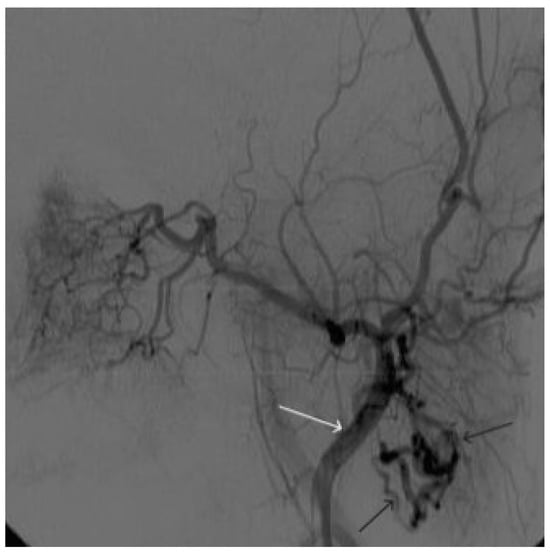

A 48-year-old male patient was admitted to the clinic with complaints of a subcutaneous volume formation in the lower jaw area on the left. Earlier, in another clinic, an attempt was made to embolize the AVM using microcoils. Angiography was performed; filling of the AVM of the soft tissues of the face in the area of the angle of the lower jaw on the left was noted. The presence of separable coils in the afferent from the previous operation was noted; however, the AVM was filled through the coils (Figure 8 and Figure 9). Total embolization of the AVM of the face soft tissues with 7.5 mL of non-adhesive composition ONYX18 was performed. Arteriovenous malformation was totally shut down (Figure 10). There were no complications. The mRs score at discharge was 0.

Figure 8. Digital subtraction angiography from the left external carotid artery, direct projection (white arrow indicates catheter in the left external carotid artery, black arrows indicate contrast AVM).

Figure 9. X-ray, direct projection (the white arrow indicates a microcatheter in the left external carotid artery, the black arrows indicate a complex of microcoils from the previous stage of embolization).

Figure 10. Digital subtraction angiography from the left external carotid artery, direct projection (white arrow indicates the left external carotid artery, black arrows indicate the boundaries of the filled AVM).